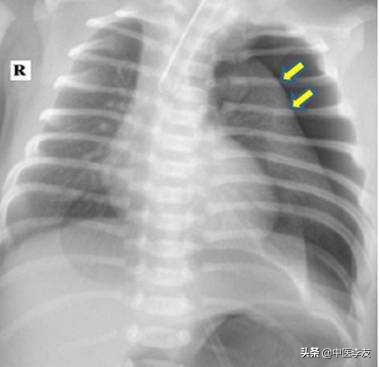

第6种是气胸:气胸一般发生在针刺肩井穴与背部背输穴,锁骨随近,前胸穴位时,针刺进深的时候发生。出现气胸以后,患者会出现胸痛,胸闷,心慌,呼吸不畅,严重的出现呼吸困难,唇颊发干,血压下降等症状。

检查除了观看病人的症状,还可以通过胸部肋间隙变宽,叩诊叩诊的音呈过轻音,气管向健侧移动,听诊的时候他的呼吸音有减弱或者消失。最好再配合x光影像进行胸透。如果胸腔的气体增加,肺部的组织受压迫,那就可以确诊为气胸。

当出现气胸的症状的时,就必须要先把针取掉。让病人采取半卧位休息,自然的呼吸,请急诊医生进行处理。